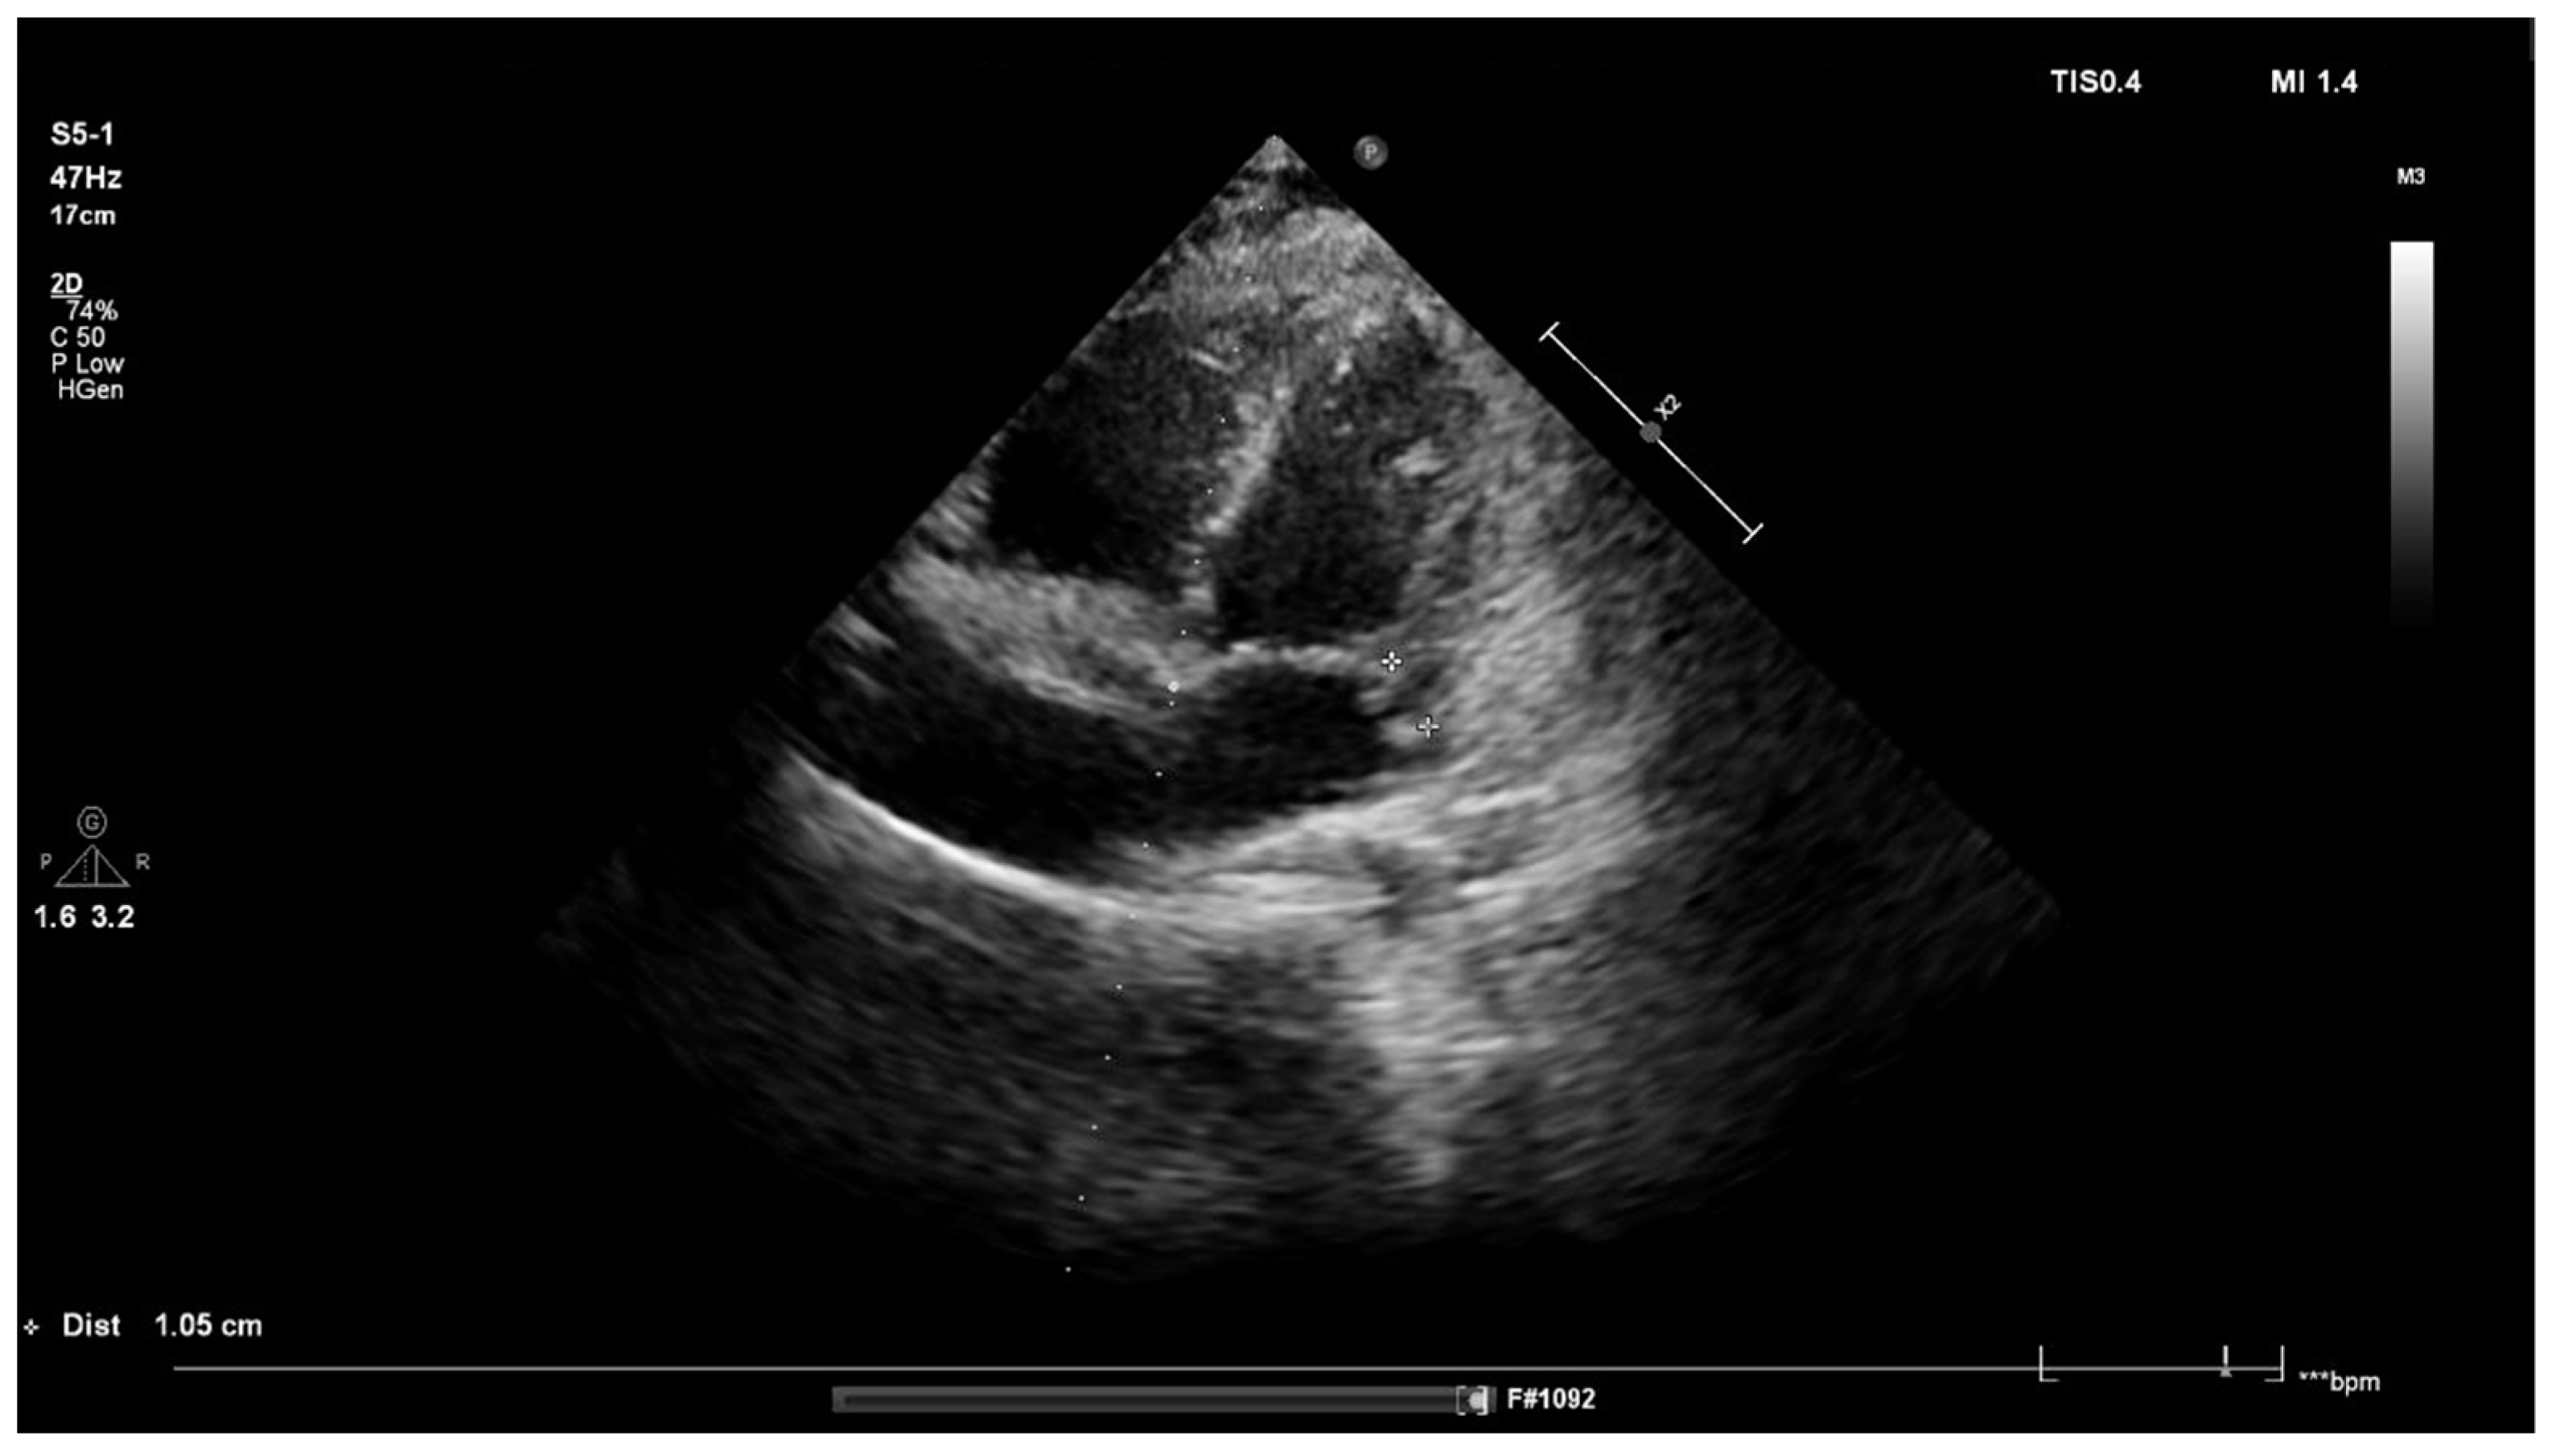

Sepsis and meningitis of S. aureus aetiology were diagnosed. Intravenous ceftriaxone and vancomycin were introduced. On the first day of hospitalization, the boy’s general condition improved, and the fever and meningeal signs resolved; however, the pain in the lumbosacral region radiating to the left lower limb persisted. On the sixth day of hospitalization, fever had risen to 38.5 °C. Laboratory tests were normalized. Magnetic resonance imaging (MRI) of the lumbosacral spine revealed the presence of skeletal muscle abscesses (Figure 1). The antibiotic therapy was changed to cloxacillin and trimethoprim with sulfamethoxazole. The abscesses were drained. S. aureus and Pseudomonas aeruginosa were cultured from a sample of the operative material, and ceftazidime was added to the treatment. Low-grade fever persisted throughout the postoperative period.

Figure 1. Magnetic resonance imaging (MRI) of the lumbosacral spine in the transverse (1a) and longitudinal (1b) position. Abscesses (marked with white arrows) of 10 × 18 mm occupying an area of 37 mm × 39 mm × 61 mm can be seen within the left iliopsoas muscle and paraspinal muscles at the L5-S1 level.

The pain in the lumbar region reported by our patient was initially associated only with meningitis; however, despite treatment and a decrease in inflammatory parameters, its persistence remained a cause for concern and required further diagnostics. MRI identified abscesses in the lumbar region. This rare condition can be primary or secondary. Primary abscesses arise as a result of the spread of pathogens from distant locations, e.g., infectious endocarditis, sinusitis or myositis, via the blood or lymphatic route, while secondary abscesses typically arise as a result of direct trauma or excessive exercise. It seems that the abscesses observed in our patient were of the former type, as an interview showed that the boy had not suffered any trauma and did not play sports [4].